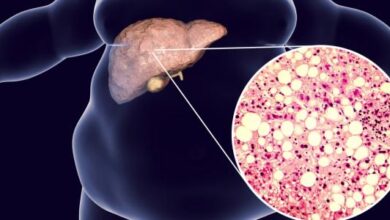

من أسباب ارتفاع إنزيمات الكبد كذلك مرض الكبد الدهني غير الكحولي (بالإنجليزية: Non-alcoholic fatty liver disease)، واختصارًا NAFLD، وهذا المرض هو مجموعة من المشاكل الصحية التي تتمثل بتراكم وتجمع الدهون في الكبد، وعادة ما يظهر لدى الأشخاص الذين يُعانون من السمنة أو حتى زيادة الوزن، وبالرغم من عدم تسبب هذا المرض في أغلب الأحيان بحدوث مشاكل حقيقية، إلا أنّ السيطرة على الحالة هو الأمر السليم للتعامل مع مثل هذه الحالات، ومن الجدير بالإشارة أنّه لا يوجد في الوقت الحاضر علاج يشفي من هذه الحالة، ولكنّ اتباع نمط حياة صحيّ قد يساعد بشكل ملحوظ في السيطرة عليها، إضافة إلى وجود مجموعة كبيرة من الأدوية التي تساهم في علاج المشاكل الصحية المرتبطة بمرض الكبد الدهني غير الكحوليّ، بما في ذلك الأدوية المخصصة لعلاج مرض السكري والسيطرة عليه، وارتفاع مستوى الكوليسترول في الدم، وارتفاع ضغط الدم، والسمنة، وغير ذلك.[٣]